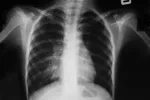

Síntomas del neumotórax

El síntoma del neumotórax más típico es el dolor que se localiza en el lado del neumotórax, normalmente en la zona de la axila, y de ahí se puede irradiar a la espalda o al hombro. También es frecuente que se note en el costado. La persona afectada puede decir que “le duele el pecho” o el costado. Es un dolor que empieza de forma brusca, de tipo punzante, como un pinchazo muy intenso. El dolor aumenta al coger aire y respirar hondo, y también con la tos que provoca el neumotórax. Esta tos suele ser seca y persistente.

Además del dolor, la persona que tiene un neumotórax se suele quejar de sensación de asfixia o falta de aire de inicio brusco. Esta disnea puede ser más o menos intensa, dependiendo del tamaño del neumotórax. Como la persona no puede respirar bien porque además le duele, la respiración suele ser más rápida de lo normal, y puede resultar imposible respirar hondo: la respiración será superficial.

La mayor o menor gravedad de los síntomas del neumotórax depende mucho del tamaño del neumotórax y de cómo estaba previamente el paciente. Así, hasta un 10% de los neumotórax pueden pasar desapercibidos al no asociarse a ningún síntoma. Una persona sana con un neumotórax pequeño puede llegar a aguantar varios días sin acudir al médico, mientras que una persona mayor con un enfisema requerirá atención de forma mucho más rápida.